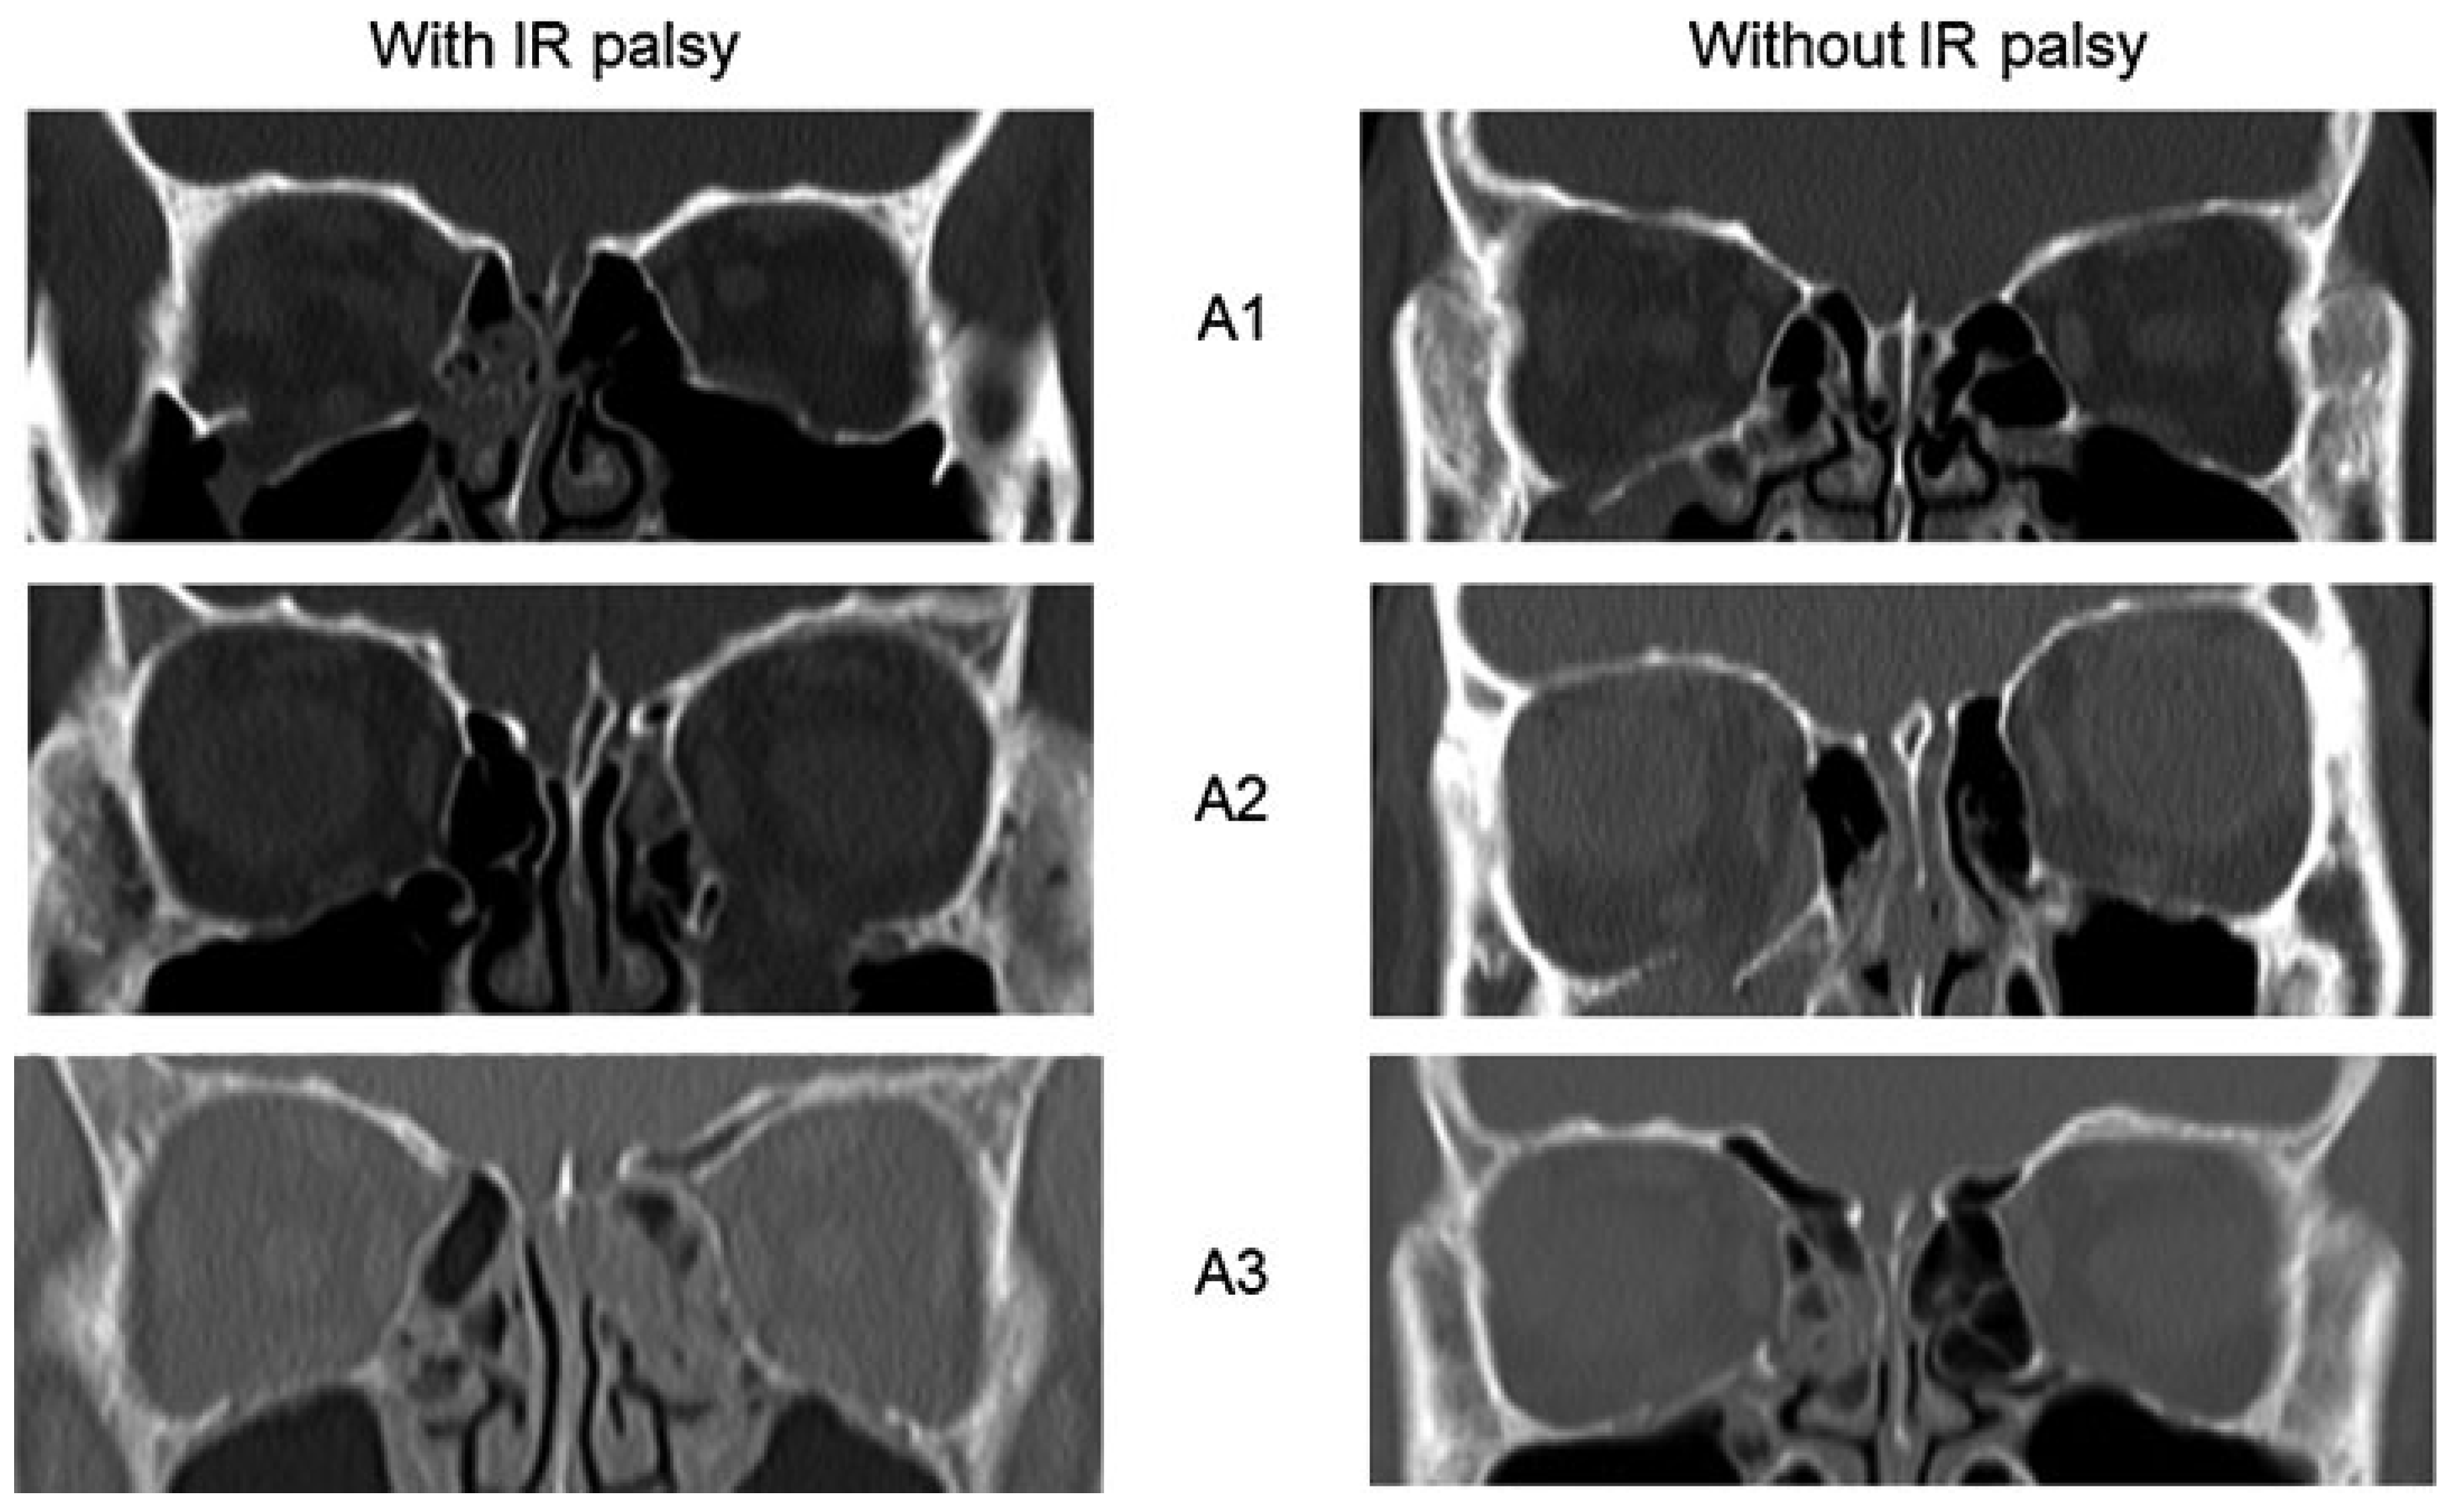

| Fracture extent, n (%) | |||

| A1 | 2 (40.0%) | 16 (37.2%) | 0.52 |

| A2 | 2 (40.0%) | 13 (30.2%) | 0.47 |

| A3 | 1 (20.0%) | 14 (32.6%) | 0.55 |